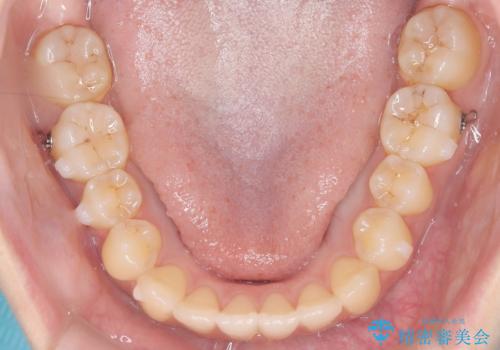

- 前歯のガタガタ(叢生)と、前歯が出ている(突出している)ことを気にされてご来院されました。精密な検査の結果、歯が並ぶスペースと、前歯を引っ込めるスペースの両方が不足していると診断。患者様のご希望に合わせ、透明で目立ちにくいインビザライン(マウスピース矯正)による治療計画を立案しました。スペースの確保は、奥歯全体を奥へ動かす遠心移動と、歯の側面をわずかに削る**IPR(歯間乳頭保護下ストリッピング)**を組み合わせて行い、前歯を効果的に引っ込めることを目指します。

今回の矯正治療では、透明なマウスピース型の装置インビザラインを使用しました。前歯を無理なく引っ込めるスペースを作るため、まず奥歯全体を後方へ移動させる遠心移動を実施。さらに、安全性が確保できる範囲で歯の側面をわずかに削るIPRを併用し、必要なスペースを確保しました。これらの処置により、前歯のデコボコが解消され、前に出ていた前歯も適切に引っ込みました。目立たない装置で治療を完結することで、叢生と突出感が解消され、機能性と審美性が向上した美しい口元を獲得していただけました。